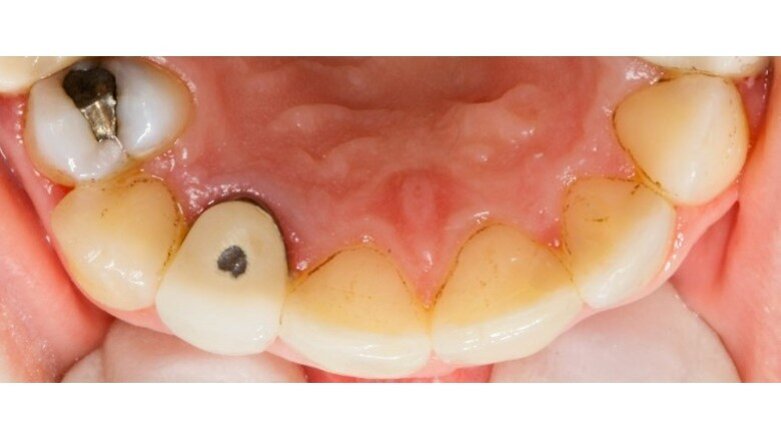

Durante la prima raccolta dati sono stati rilevati 31 siti totali che presentavano black stains (Tab. 4), 13 siti nel controllo ad un mese dall’inizio dell’assunzione di “Lautoselle” (Tab. 5), infine, 18 siti una volta terminata l’assunzione di “Lautoselle” (Tab. 6); di questi ultimi tutti i siti che presentano black stains sono di primo grado e molto meno evidenti rispetto alla prima raccolta dati. Rispetto al caso precedente i risultati sono stati meno soddisfacenti: i siti che presentano black stains corrispondono al 55,8% rispetto a quelli iniziali già al termine del periodo di assunzione di “Lautoselle”. Va in ogni caso considerato che i pigmenti presenti sono molto evidenti e che, per ammissione del paziente stesso, l’assunzione del probiotico non è stata scrupolosa (Figg. 5a-5c).

Fig. 5a - Fotografia del quarto sestante linguale al primo rilievo delle black stains.

Fig. 5b - Controllo dopo un mese.

Fig. 5c - Controllo a tre mesi.